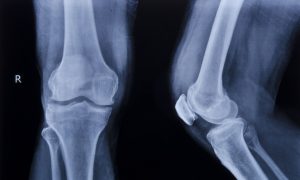

Recently, placebo-controlled surgery trials have been used. In perhaps the most famous of these, American surgeon Bruce Moseley found 180 patients who had such severe knee pain that even the best drugs had failed to work. He gave half of them real arthroscopy and the other half placebo arthroscopy.

Patients in the placebo arthroscopy group were given anesthetics and a small incision was made in their knees, but there was no arthroscope, no repairing of damaged cartilage, and no cleaning out of loose fragments of bone.

To keep the patients ignorant about which group they were in, the doctors and nurses talked through a real procedure even if they were performing the placebo procedure.

The fake surgery worked as well as the “real” surgery. A review of over 50 placebo-controlled surgery trials found that placebo surgery was as good as the real surgery in more than half the trials.